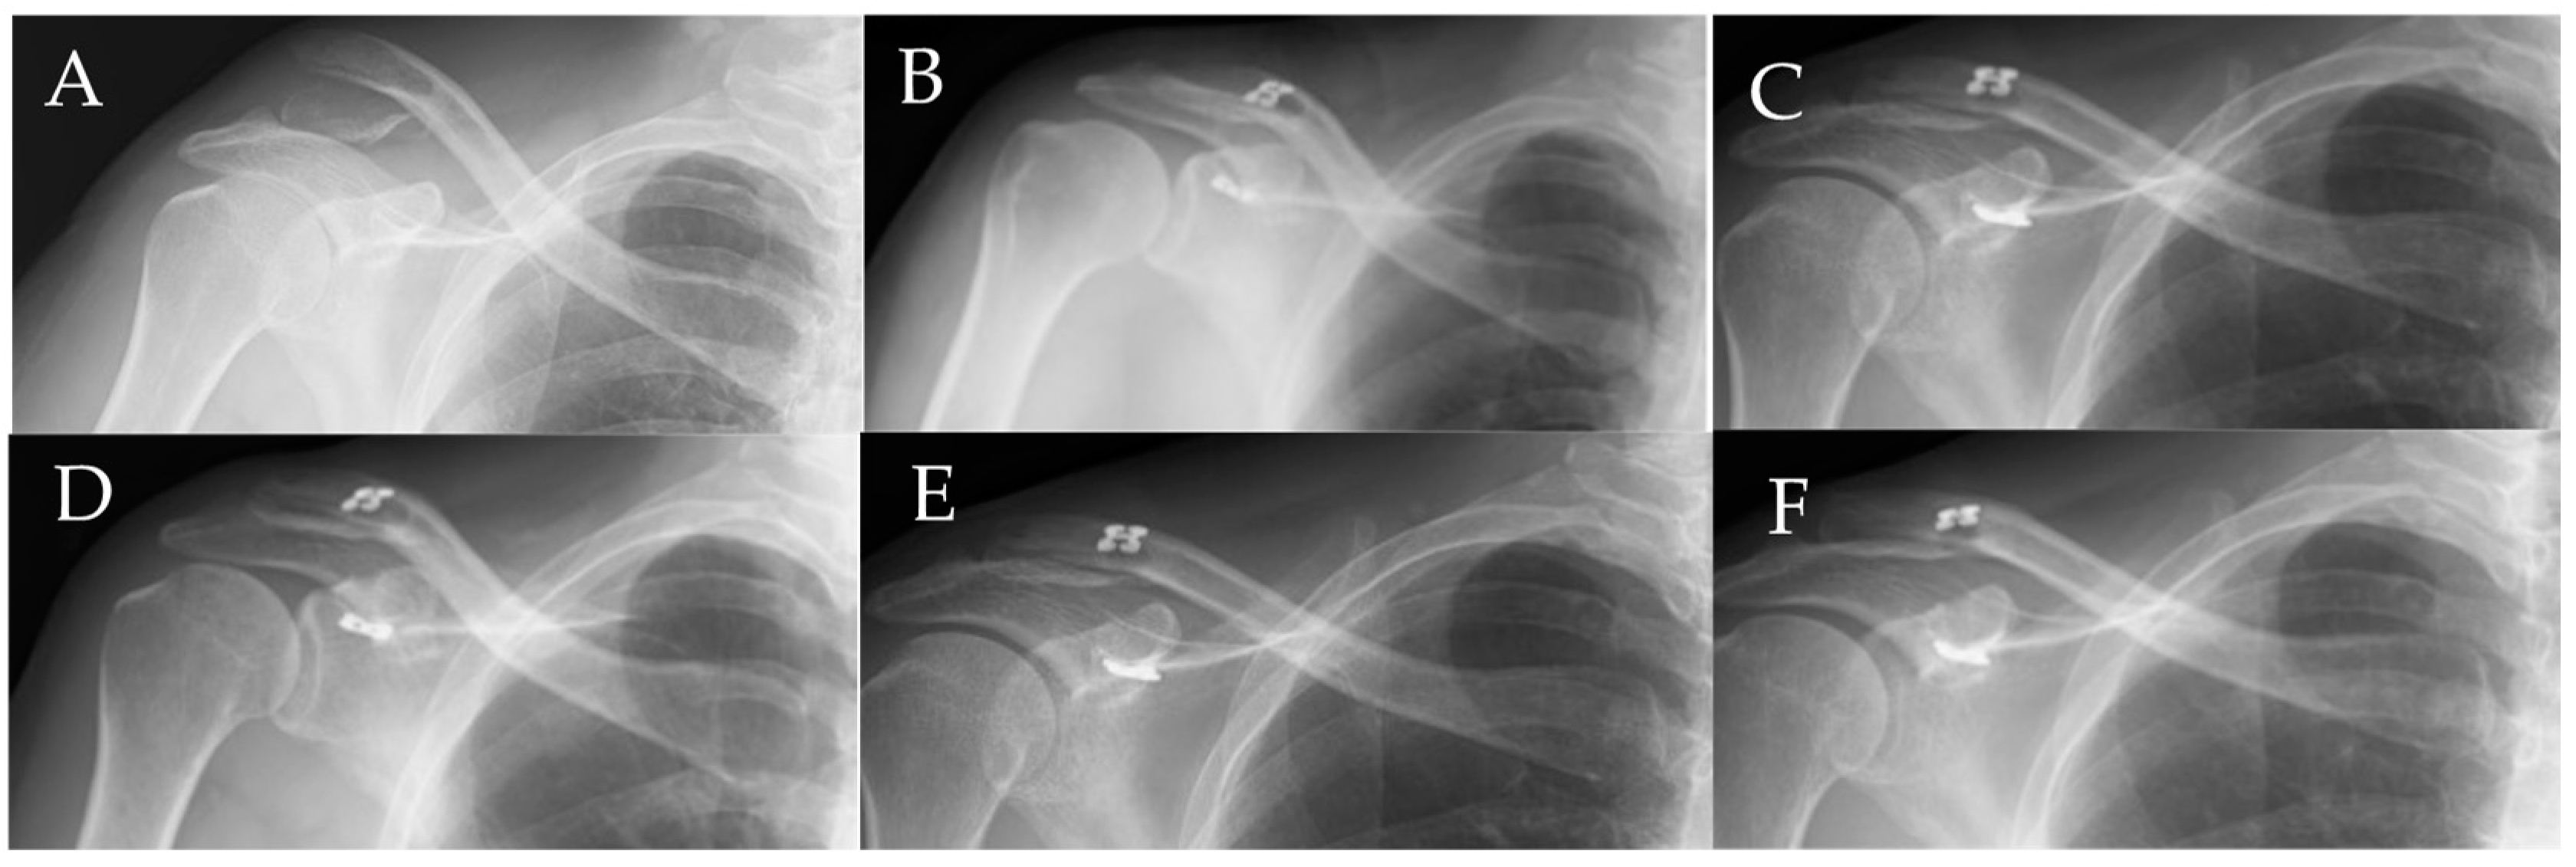

All six patients showed complete bony union, with two showing union at 3 months and four showing union at 6 months. Representative X-rays before and after surgery are shown in Figure 3.

Figure 3. Representative X-rays before and after surgery. (A) Preoperative radiograph. (B) Postoperative radiograph immediately after surgery. (C) Radiograph at 3 months after surgery. (D) Radiograph at 6 months after surgery showing complete bony union with subsidence of the clavicular button. (E) Radiograph at 9 months after surgery showing no dislocation. (F) Radiograph at 12 months after surgery showing no dislocation.